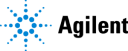

The only constant in healthcare is change. Dendi’s powerful

and user-optimized software platform equips clinical labs

with the tools needed to move forward with confidence.